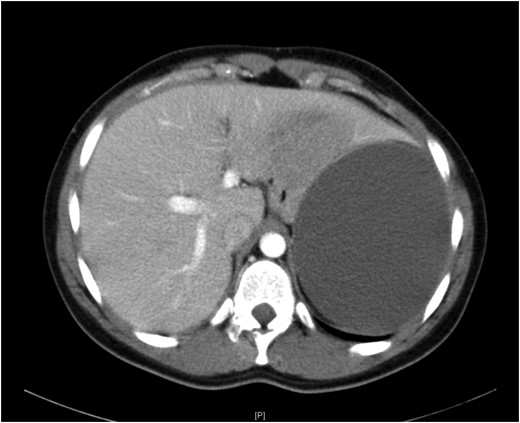

A 19-year-old female presented with a 2-day history of severe left upper abdominal pain. There was no known history of abdominal trauma or travel outside the UK. She was systemically well, had a soft abdomen with exquisite tenderness at the left upper quadrant and loin regions. The provisional blood tests, hydatid serology and chest and abdominal X-rays were unremarkable. An ultrasound scan showed a large splenic cyst with no increase in vascularity on Doppler assessment, while an intravenous contrast-enhanced CT scan showed a 12.5 × 9.7 × 10.7 cm well-defined cystic mass arising from the upper pole of the spleen (Fig. 1) with multiple fine echogenic shadows and medial displacement of the stomach and the left kidney (Fig. 2). Findings were consistent with the diagnosis of a simple splenic cyst. The patient was scheduled for an urgent laparoscopic de-capsulation, and received triple vaccination (meningococcal, pneumococcal and Haemophilus influenzae type B). Although 2 weeks are recommended between vaccination and splenectomy should this be needed, we proceeded to surgery after 10 days from vaccination as the patient was considerably troubled with abdominal pain and we were confident that a total splenectomy could be avoided.